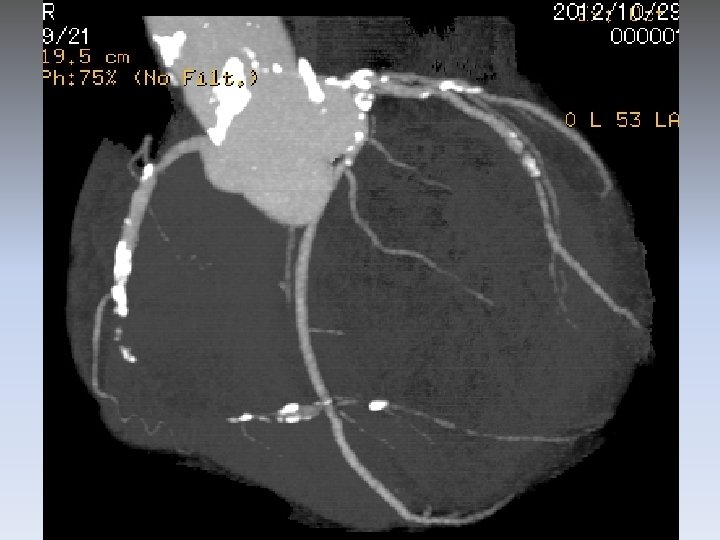

UCG (10/10/2012) LVEF 36%, LVDD 64 mm diffuse hypokinesis inferior akinesis BNP 2220 pg/ml

UCG (10/10/2012) LVEF 36%, LVDD 64 mm diffuse hypokinesis inferior akinesis BNP 2220 pg/ml CTCA showed

RCA #2 long CTO LAD #6 90% LCX #13 90%